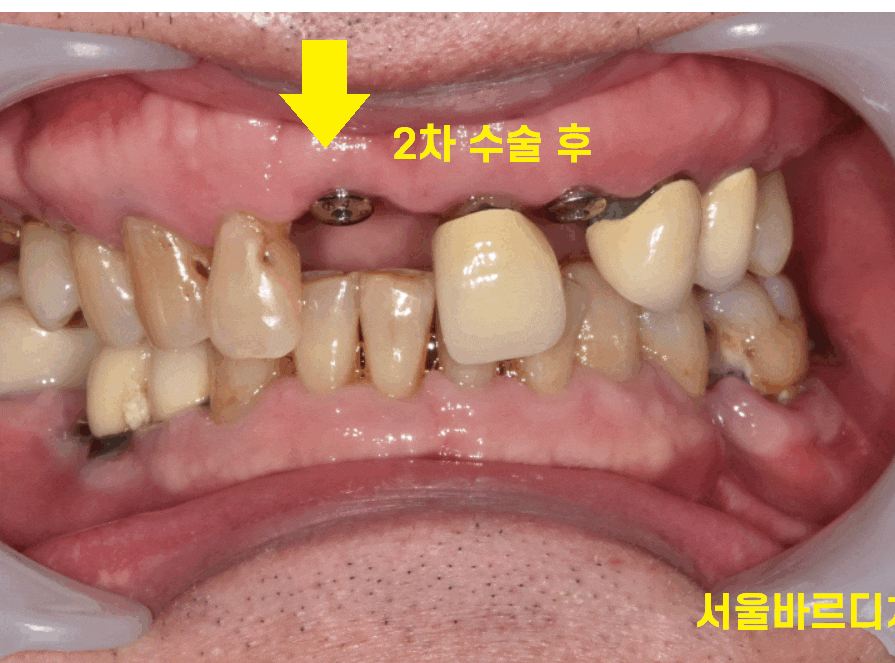

꺼내고 나면 이런 모습이에요!

240416

작은 기둥을 연결하는 것이 임플란트 2차 수술 과정입니다.